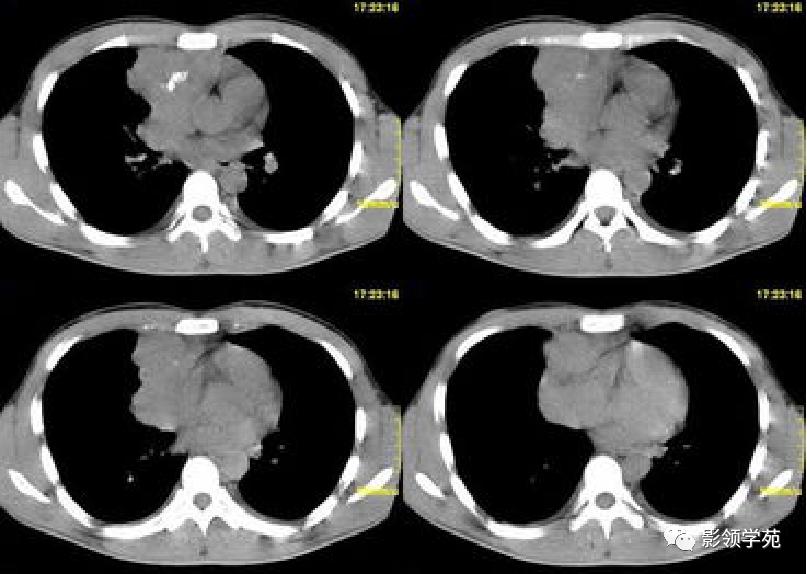

- 纵隔恶性生殖细胞瘤相对少见,其中以精原细胞瘤最多见,好发于男性青少年。

- 发现时肿块常较大,多为分叶状,边缘不规则,极少含脂肪及钙化成分,如有出血及坏死可表现为密度不均匀,肿块与邻近结构间脂肪间隙消失,常侵犯或推压邻近器官。

肿块周围脂肪间隙消失,与邻近结构分界不清

分叶状,边缘不规则,与邻近结构脂肪间隙消失